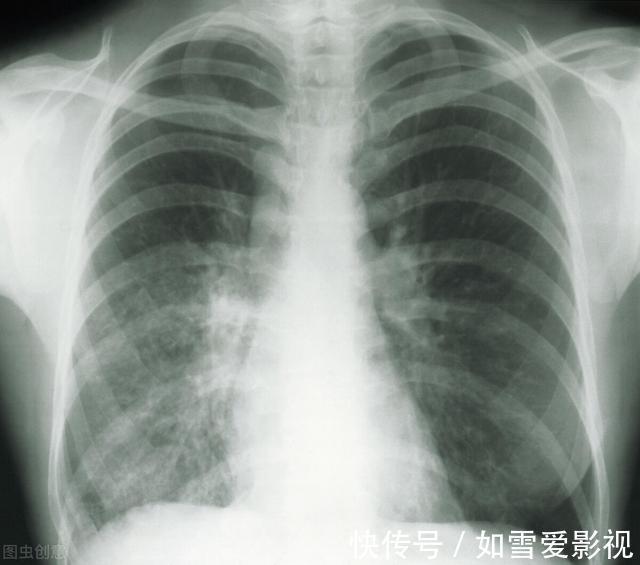

就医|女子双肺多发结节,一个已癌变!一旦查出这结节,建议尽快就医

随着人们生活水平和健康意识的提高,期体检已成为常规。当拿到体检报告时,很多人都为报告上的肺部有"磨玻璃影”字样而纠结不已。患者陈女士就是一个典型的例子。近两年来,肺结节如同一块磐石,一直压在陈女士的心头。两年前,陈女士在体检中意外查出肺结节,且双肺多发,这让有肺癌家族史的陈女士慌了神。

自己才45岁,会不会已经罹患肺癌?医生告诉她,肺结节并不一定是肺癌,且结节尚小,可先跟踪观察。这一观察就是两年。近期,陈女士来到医院复查,薄层CT扫描结果显示,陈女士左肺为磨玻璃结节,且有增大现象,考虑恶性可能度高。保险起见,医生建议手术摘除。术后病理结果显示,陈女士体内的肺结节,最大的仅有0.9cm,但已发展为早期浸润肺癌,一个为原位腺癌,0.4cm,其他的均为炎症性结节。